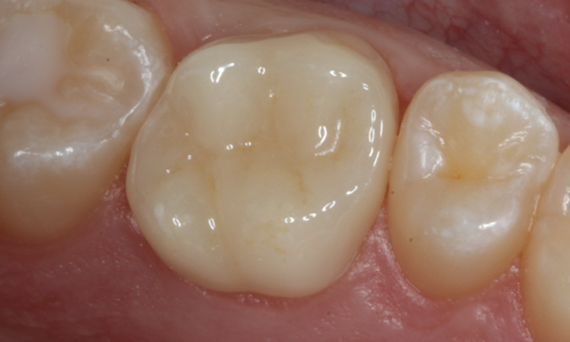

After

Chairside-fabricated restoration made from an advanced lithium disilicate ceramic, CEREC Tessera.